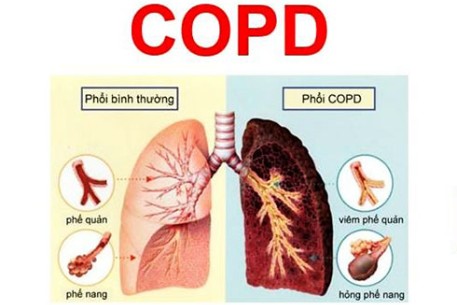

Nhiệt độ môi trường thay đổi rất dễ bùng phát các đợt cấp của Bệnh phổi tắc nghẽn mạn tính

Theo Bộ Y tế, bệnh phổi tắc nghẽn mạn tính (COPD) là nguyên nhân gây tử vong đứng thứ 3 trên thế giới. Tại Việt Nam, tần suất mắc bệnh phổi tắc nghẽn mạn tính trung bình và nặng đứng cao nhất trong khu vực châu Á Thái Bình Dương. Một điều tra cho thấy có tới 3,1% số người trưởng thành ở nước ta từng được chẩn đoán mắc bệnh này.